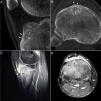

Cortes sagital (A) y axial (B) de tomografía computarizada de la rodilla derecha, que evidencian una lesión osteolítica en la zona subendostal de la tuberosidad tibial anterior, con matriz osificada a modo de «nidus», compatible con osteoma osteoide (flecha), rodeada por importante esclerosis en el hueso medular circundante (asteriscos) y reacción perióstica sólida en la cortical adyacente (cabezas de flecha). En los cortes sagital (C) y axial (D) de la resonancia magnética en las secuencias T1-SPIR (Spectral Presaturation with Inversion Recovery) posgadolinium se observa captación de contraste perilesional en forma de anillo (flecha), así como en el edema óseo circundante (asteriscos) y la grasa de Hoffa (cabezas de flechas).